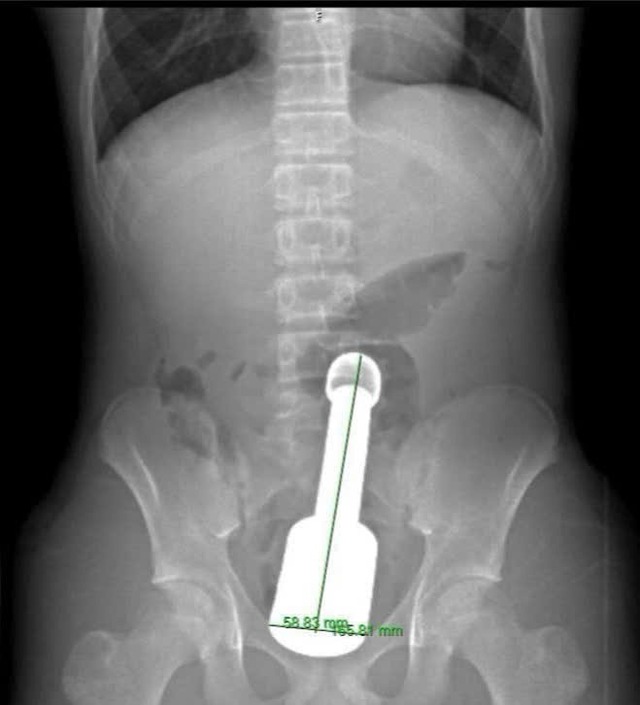

差點破裂!15歲少年誤將「18公分金屬異物」塞入直腸 醫驚:遠超括約肌負荷

越南河東醫院的醫師,近日成功從一名15歲男學生的直腸內取出一支長18公分、直徑6公分的金屬棒狀物,讓患者避免接受開腹手術。

根據外媒報導,男學生因下腹部劇烈疼痛被緊急送醫,醫師檢查後發現,一個大型異物已深入直腸並壓迫骨盆區域器官,目前仍不清楚男學生為何會出現這樣的行為及當時的情況。醫療團隊表示,最大的困難在於棒狀物的尺寸,遠超過青少年肛門括約肌的最大承受範圍。異物體積大且重量重,產生了類似「真空效應」,使腸壁緊貼異物表面。如果僅用拉力強行取出,極可能造成直腸破裂。

醫師們採取謹慎的處置方式並密切配合技術操作,一名醫師固定異物位置,另一名醫師將工具插入異物後方並注入空氣,成功消除吸附力,使手術團隊能夠安全地將棒狀物取出,同時完整保留患者肛門括約肌的功能。目前少年健康狀況穩定,檢查顯示直腸黏膜僅有輕微擦傷,消化功能正逐漸恢復,預計幾天內即可出院。